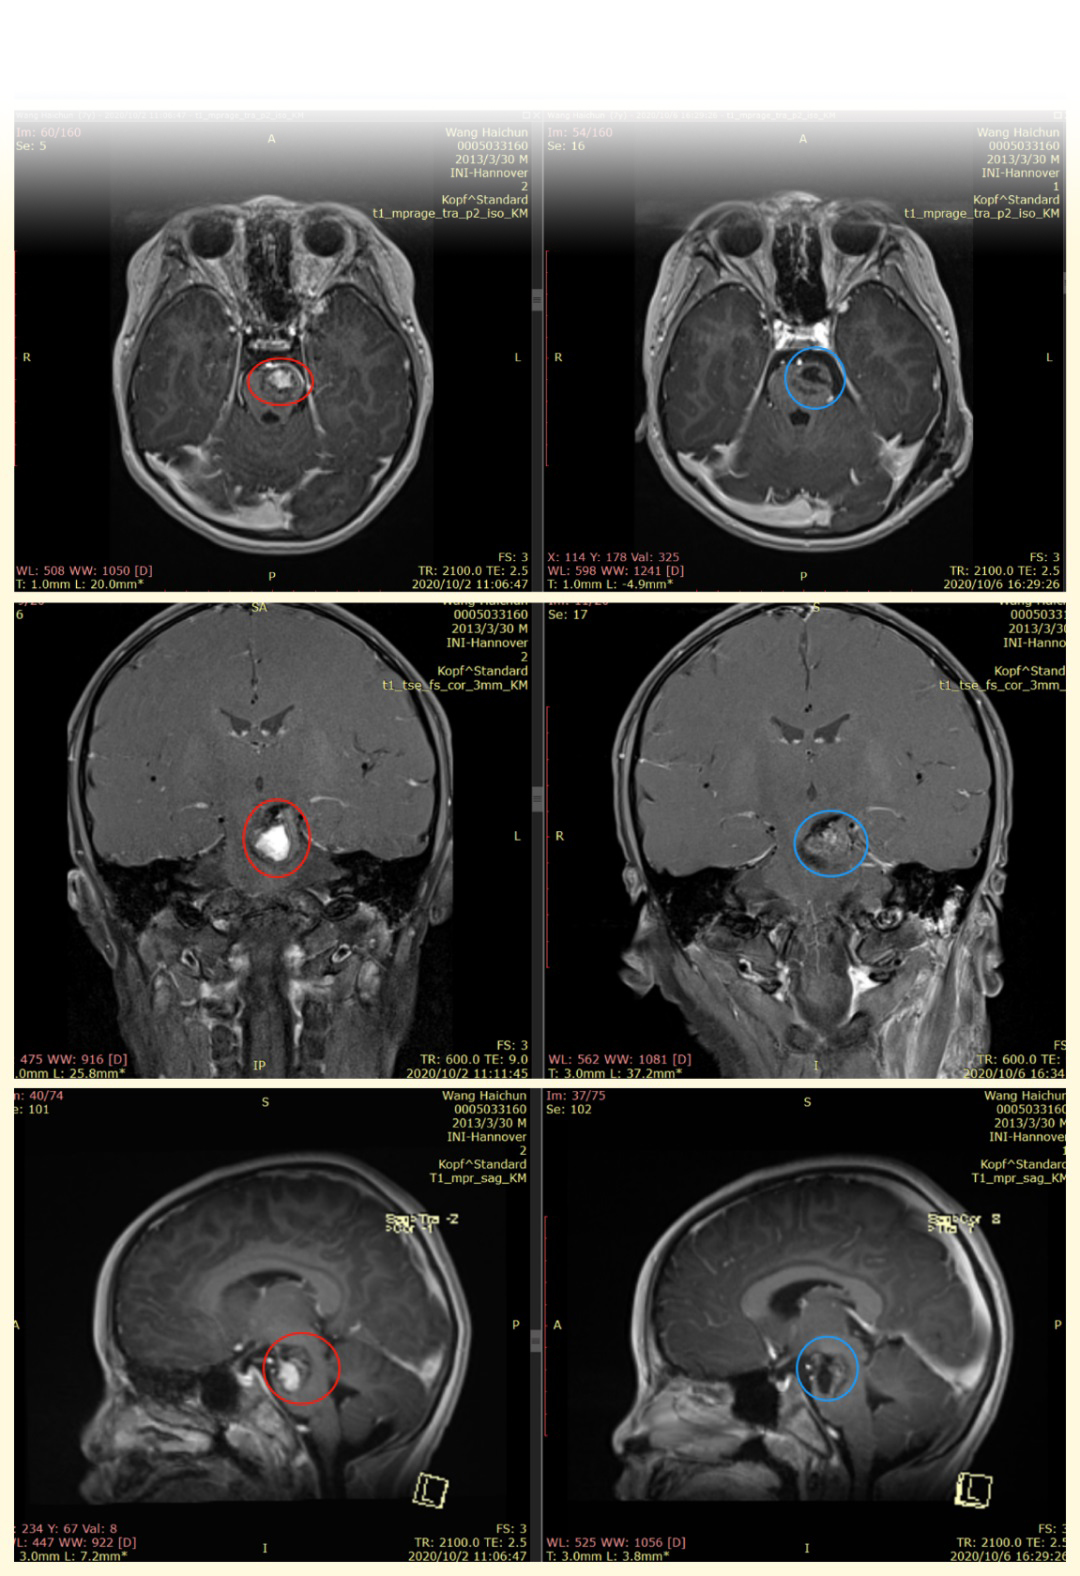

腦干海綿狀血管瘤影像

陽陽病情復發(fā)影像資料顯示:腦干不規(guī)則異常信號影,面大,T1WI以高信號為主,T2WI低信號,彌散不受限。

腦干海綿狀血管瘤術前術后對比